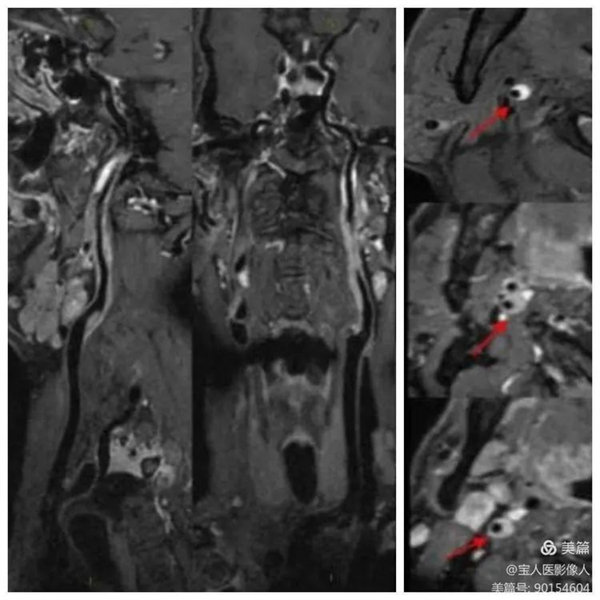

02、颈动脉粥样斑块磁共振成像

67岁男性,颈动脉斑块成像显示:颈总动脉及颈内动脉粥样斑块,偏心性生长伴出血,MRI诊断不稳定性斑块。

常规TOF-MRA显示颈动脉管腔明显局部狭窄

冠状位显示颈内动脉起始段管壁增厚,呈高信号

增强明确管壁增厚原因

平扫和增强对比明确管壁增厚病因,提示:粥样斑块,并内出血,多系不稳定斑块

头颈部血管增强磁共振成像(CE-MRA)和血管壁成像(HR-VWI)主要临床应用:

1、管腔狭窄位置及程度评估;分析粥样硬化斑块的成分和稳定性、辅助卒中病因分型及明确发病机制。

2、评价斑块负荷及重构情况、斑块内成分量化评估内科治疗疗效。

3、确定斑块位置评估穿支血管情况、辅助支架定位。

4、其他缺血性卒中病因诊断,如血管炎、夹层、烟雾病等。

5、动脉瘤检出及破裂风险预测。